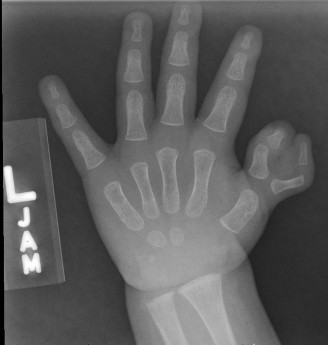

CASE 30 An 11-month-old patient is brought to you by his parents for “two thumb…